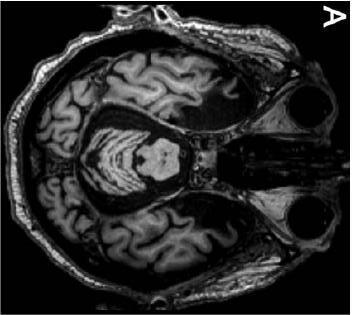

Las primeras resonancias magnéticas estructurales (RMNe)

se realizaron en 1992 (a los 66 años de edad) y 1993. La lesión dañó la mayor parte del complejo amigdaloide, la corteza entorrinal, parte de la corteza perirrinal, las porciones uncal y rostral del hipocampo y parte de la corteza parahipocampal.

Tomado

de Augustinack, J. C. et al., (2014). Hippocampus, 24, 1267-1286.